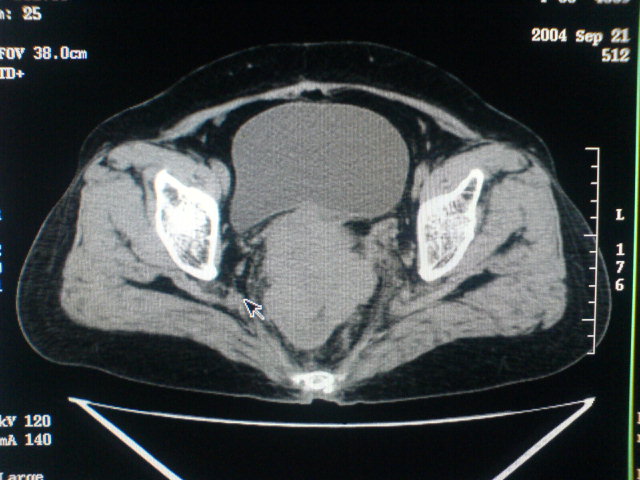

患者为老年女性,肿块最大层面不是位于宫颈,但宫颈偏后方有一囊状低密度影,肿块主要位于乙状结肠及直肠,所以考虑乙状结肠及直肠癌浸犯宫颈可能性大。

患者女性60岁 病史不详

宫颈癌侵犯直肠可能

考虑子宫内膜癌浸犯直肠。

考虑直肠癌侵及宫颈可能;建议增强扫描。

支持考虑宫颈癌上下前后通吃

考虑:直肠及乙状结肠癌侵及宫颈,囊性转移(假性粘液瘤)

支持宫颈癌侵犯直肠。

考虑直肠及乙状结肠癌侵犯邻近结构。